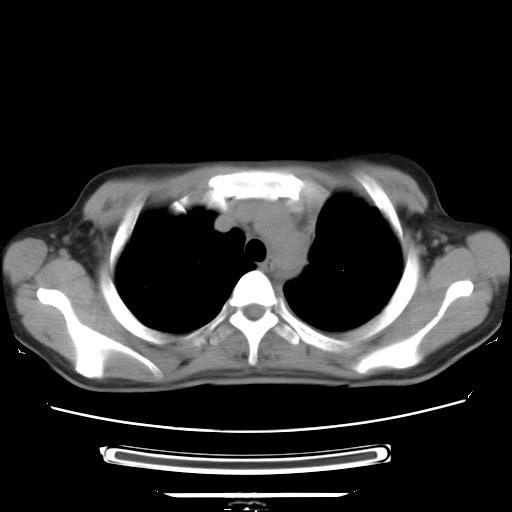

女,29岁,胸部不适,在外院胸片提示胸腔积液,到我院ct检查。

纵膈窗